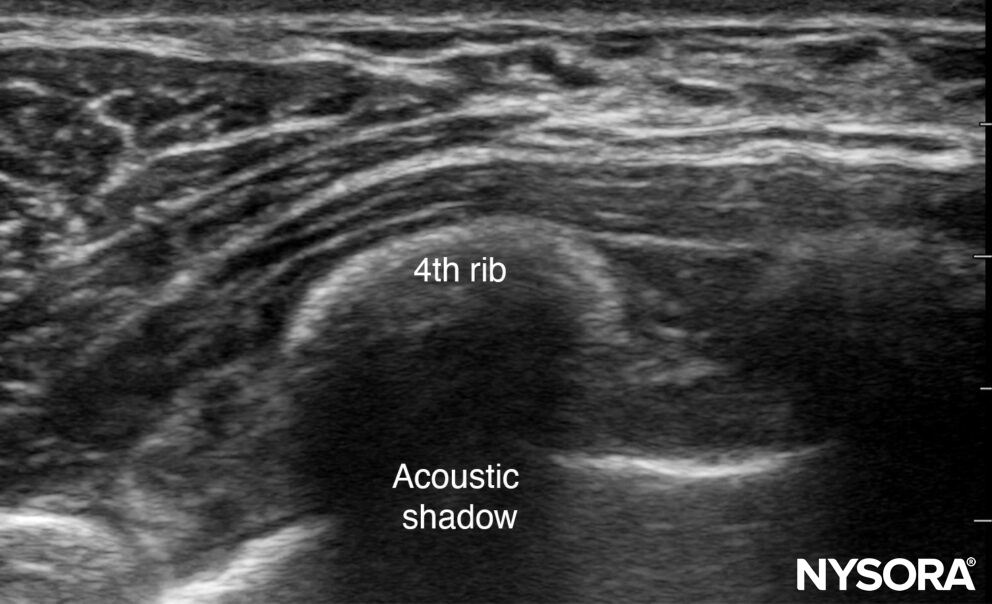

Acoustic shadowing

Acoustic shadowing is caused by a structure that is more or less dense than soft tissue (e.g., bone or lung). It will result in the loss of the ultrasound signal due to scattering and reflection of the ultrasound beam.

Acoustic shadowing.